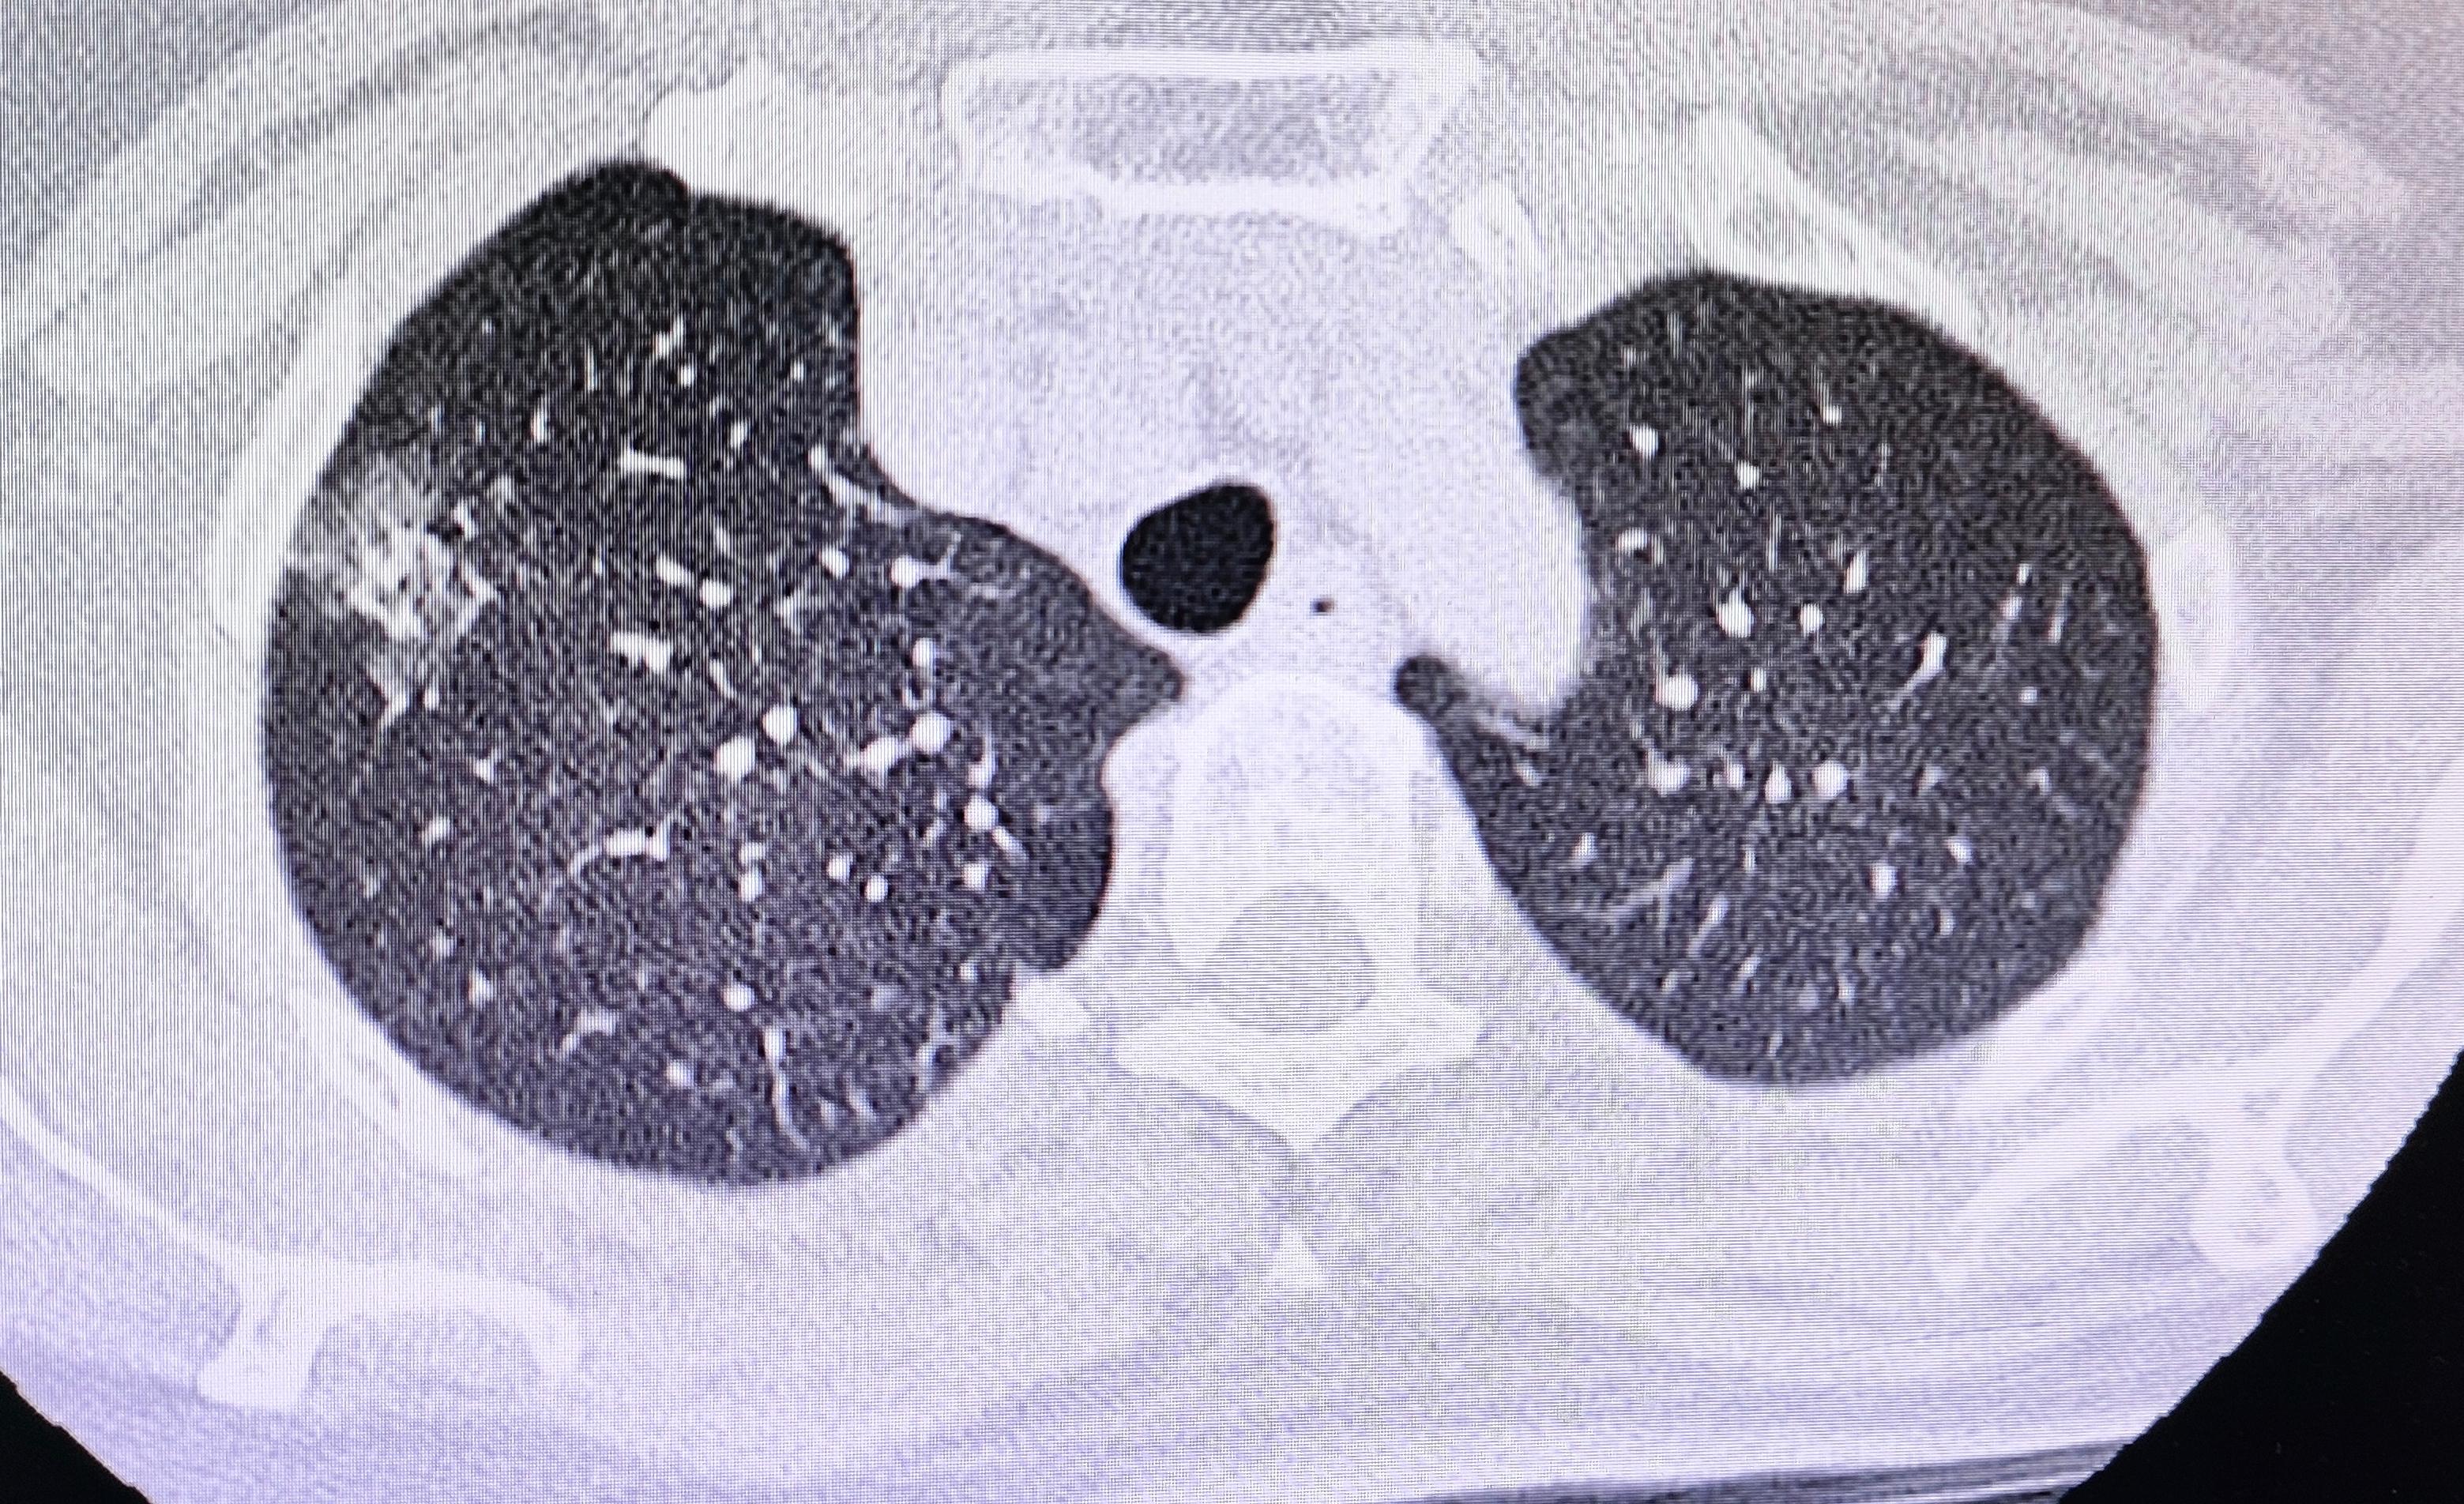

你知道多发肺结节长什么样吗?

肺结节大小的分类

肺部结节